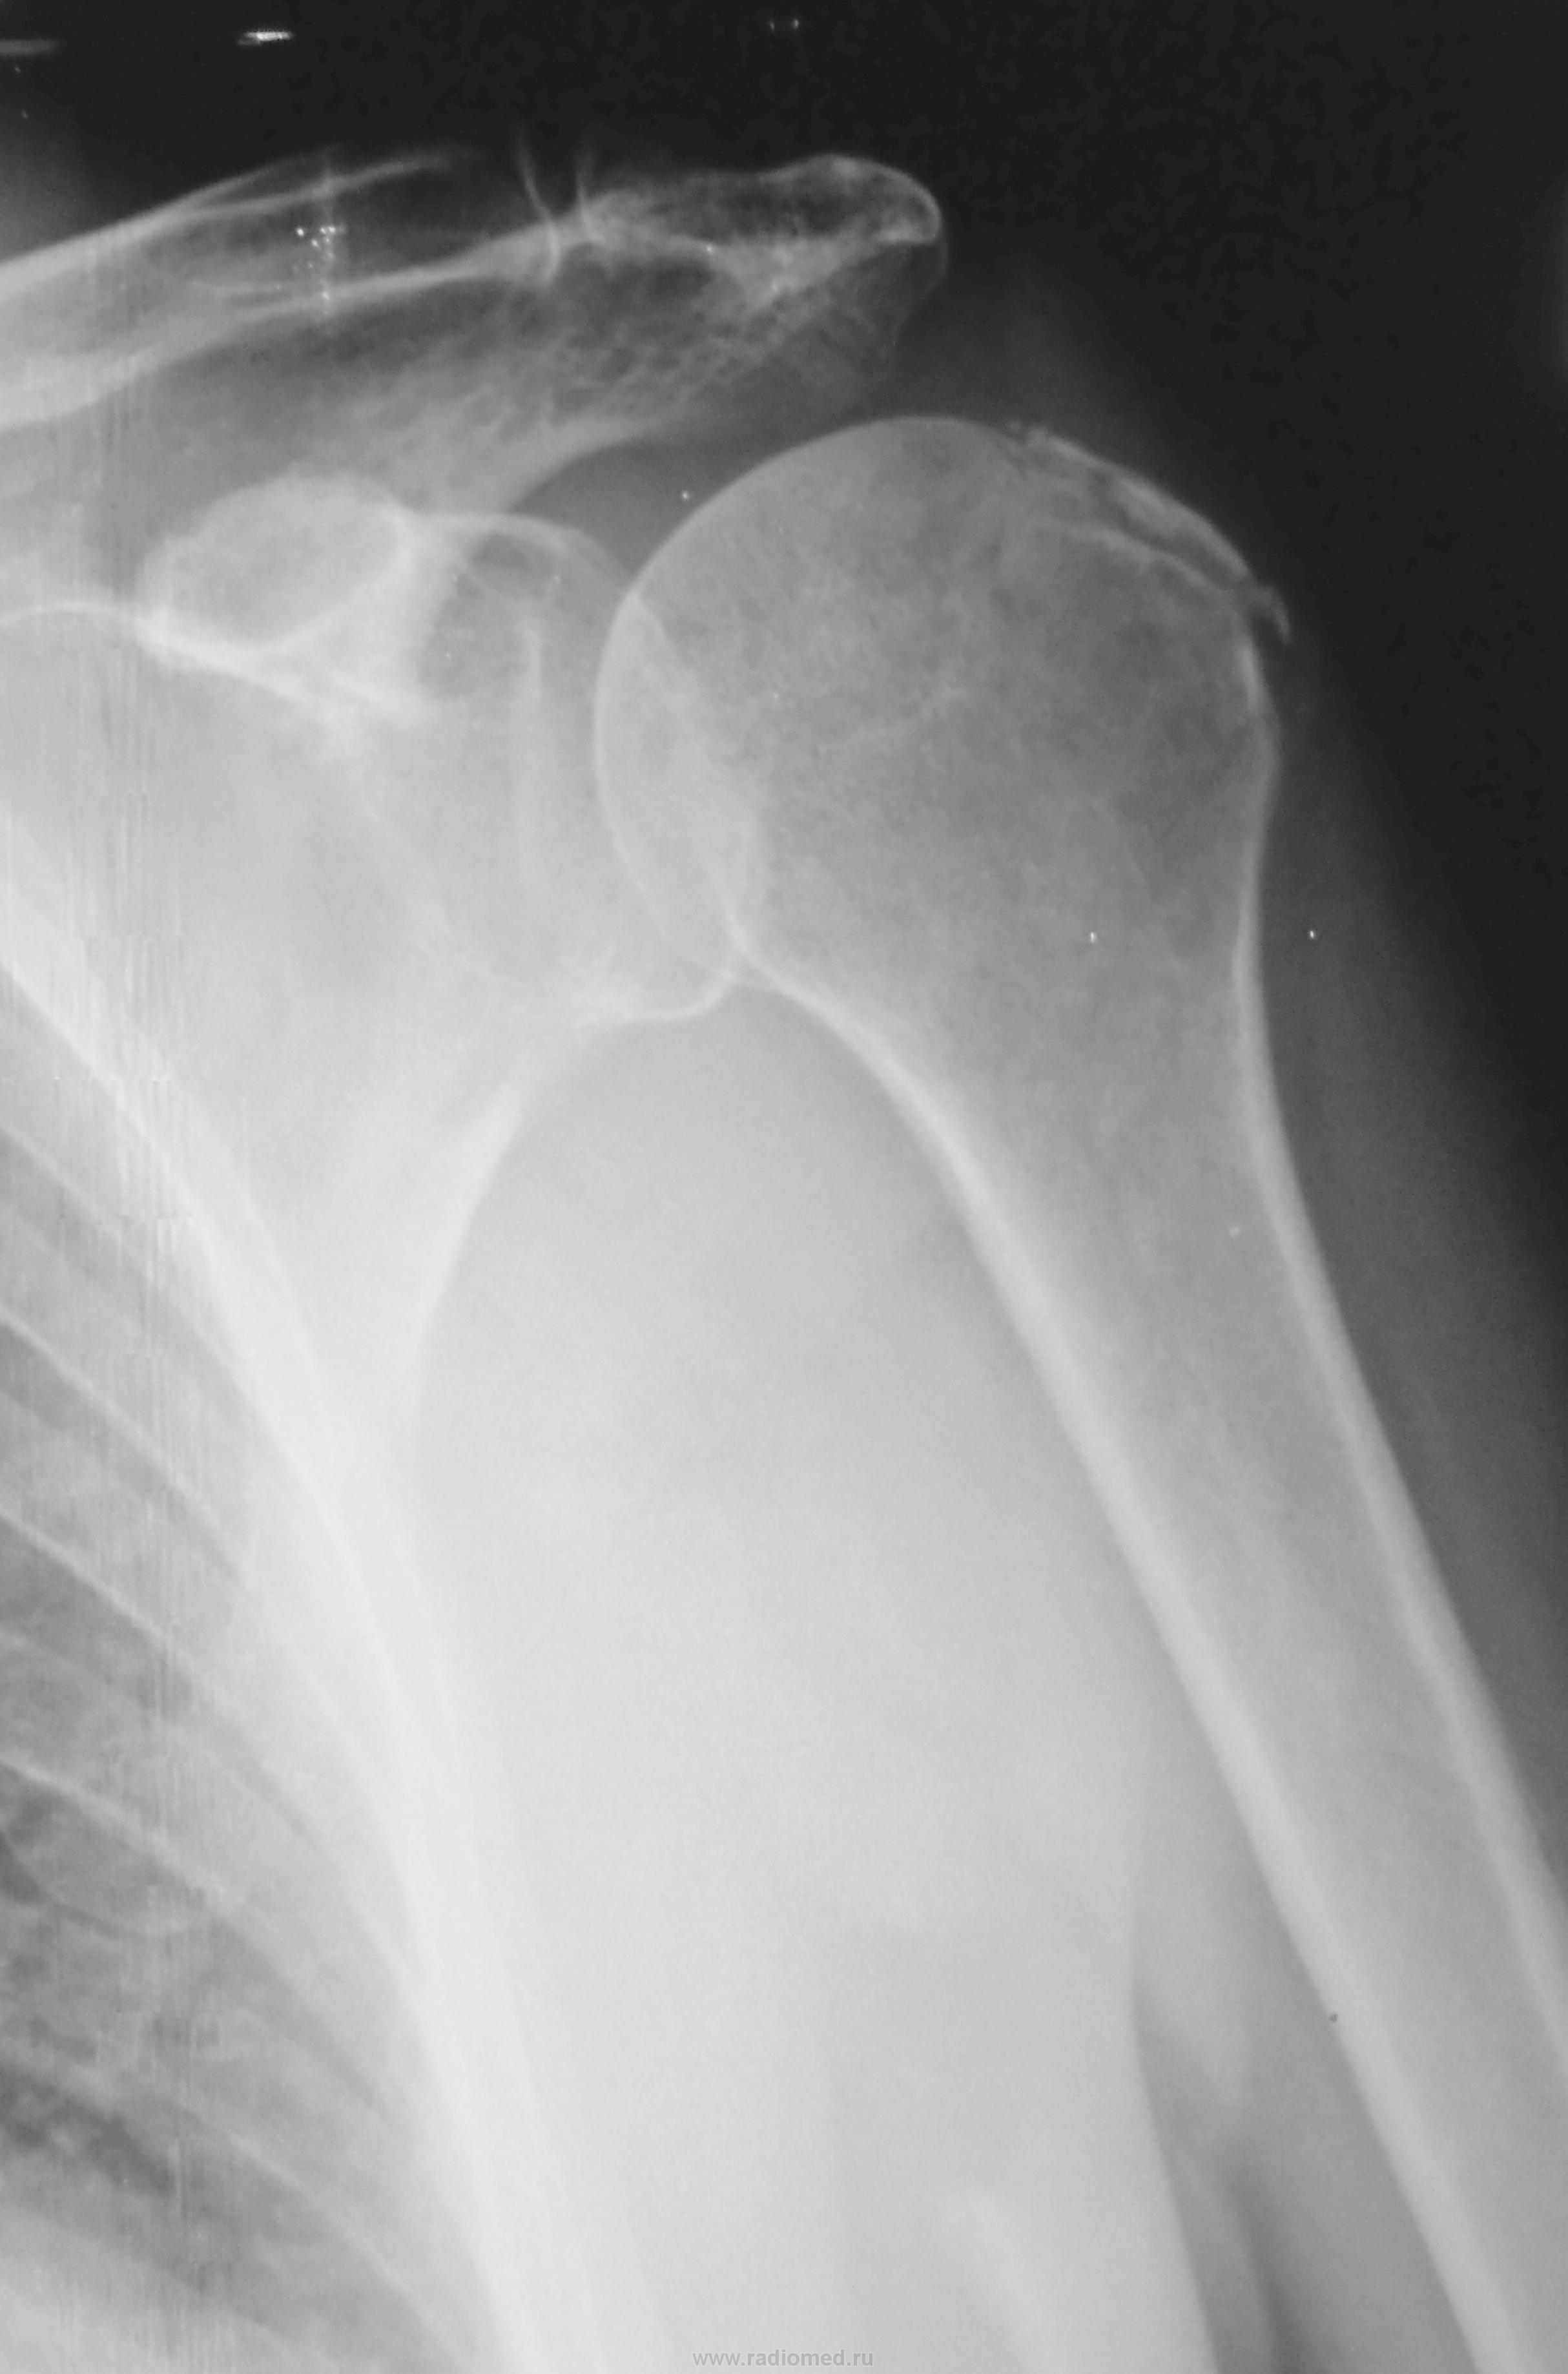

Перипроцесс.

Хирургом травма расценана как свежая.

Думаю, что здесь несколько недель. А может сумка обызвествилась?